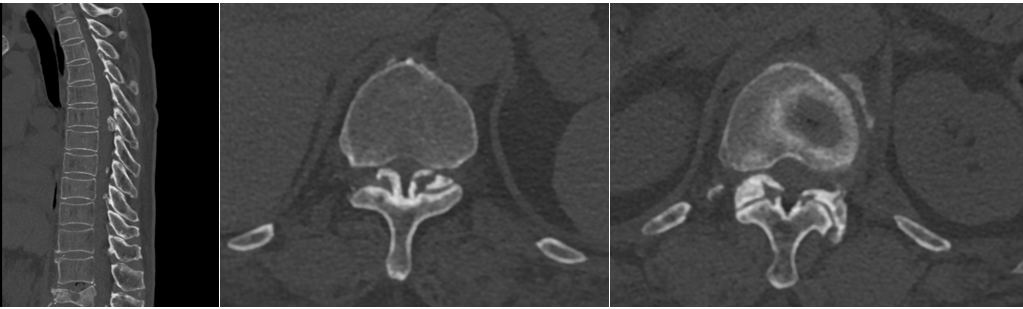

胸椎管狭窄黄韧带骨化症是一类高致残性疾病,薄薄的神经如同松软的豆腐,任何一点损伤都可能导致不可逆的后果,切除骨化的黄韧带就好比在刀尖上表演舞蹈。姜主任将最新的UBE技术应用到王阿姨的手术治疗中,通过3个1cm的小切口在内镜下顺利从胸椎后方对T5-T7椎板完成了切除减压,并通过薄化技术一点一点切除骨化的黄韧带,用时153分钟顺利完成了“内镜下胸椎椎板切除减压术+黄韧带切除术”,术中出血60ml。术后,患者下肢麻木症状明显好转。在医院稍作休养后,即顺利康复出院。这次的UBE微创手术让王阿姨的印象尤为深刻,切实体会到了微创手术的神奇。

胸椎管狭窄症是指先天性或后天退变因素等导致的胸椎管横断面积缩小,脊髓受压而产生的一系列症候群。胸椎管狭窄症常引起严重的脊髓损害,导致下肢瘫痪等严重后果。后天性胸椎管狭窄症最常见的病因是胸椎黄韧带骨化。

胸椎管狭窄症最有效的治疗手段是通过手术扩大椎管,但该手术风险极大,极易引起瘫痪等手术并发症。传统的开放性手术存在创面大、失血多、破坏脊柱稳定性、术后恢复慢等问题,是脊柱外科难度系数最高的手术之一。而运用UBE技术治疗胸椎管狭窄症,不仅手术创面小,而且在内镜放大照明良好的视野下操作更精准、更安全。此外,该手术只切除了致压的部分组织,并未影响病变节段的稳定性,最大限度的减少了脊柱后路融合的需求。这项全新的手术技术为胸椎管狭窄症的治疗提供了新的选择,也为患者带来了更好的治疗效果和术后体验。